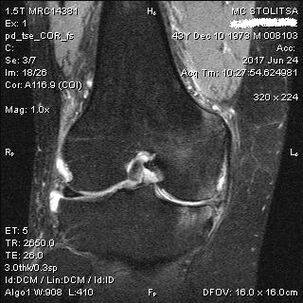

Diagnosis and treatment of osteoarthritis of the knee joint

The diagnosis of arthrosis of the knee joint takes place in the office of a rheumatologist or orthopedist.The doctor examines the affected joint, palpates it, listens to complaints and asks additional questions.Performs various tests - for example, asking the patient to bend their leg or take a few steps.Then, if it is necessary to clarify the stage of the disease or the nature of the pathological changes, he will refer you for additional studies.For example, for computed tomography or radiography.